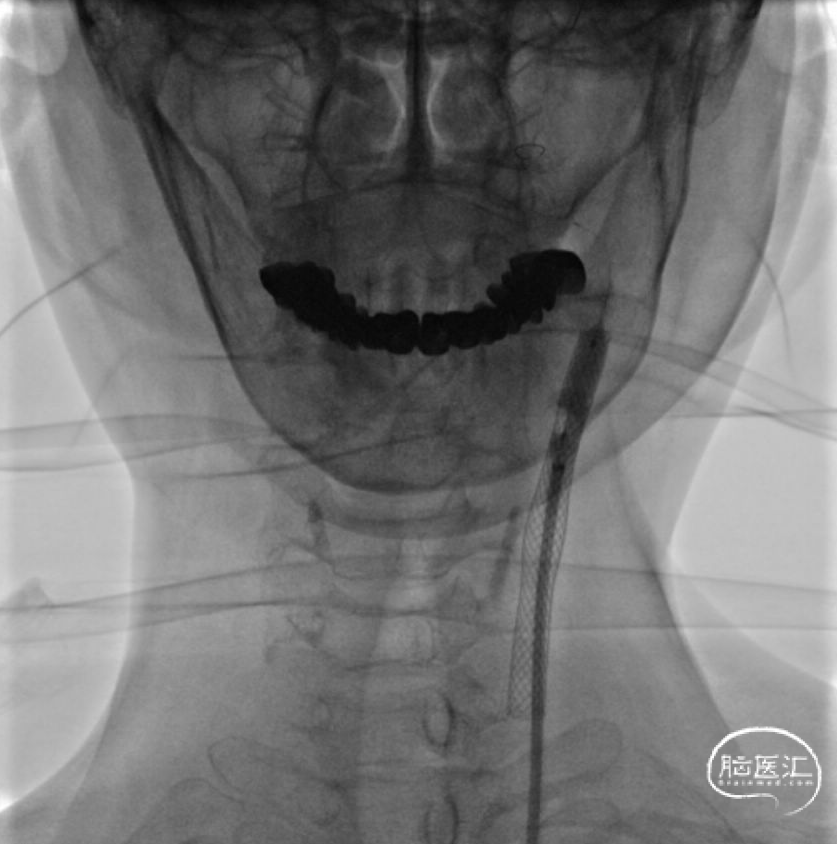

dTRA-6F薄壁鞘-置入泥鳅导丝交换后引入易介80cm-088薄壁长鞘

撤除内衬后088薄壁长鞘保持稳定未打折

Filter wire近颈内动脉